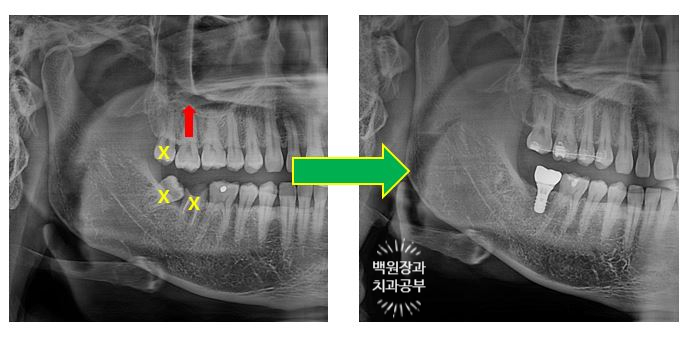

먼저 전체 치과용 파노라마 엑스레이부터 볼까요?

어색하게 깡뚱하게 있는 치아가 보이시나요?

아래턱 오른쪽 두번째 큰어금니가 신경치료는 되어있지만, 이미 뿌리만 남은 상태로 오셨어요.

노란색으로 동그랗게 표시해놓은 치아가 오른쪽 아래 두번째 큰어금니입니다.

오른쪽 사진을 보시면, 분홍색 재료가 신경치료 때 쓰이는 재료인데 모두 드러나 있어요.

어쩔 수 없이 빼야하는 상황입니다.

오른쪽 아래 두번째 큰어금니가 뿌리만 남아있은지가 너무 오래되서, 그 공간으로 짝꿍 치아인 (대합치) 오른쪽 위 두번째 큰어금니가 꽤나 내려와 있었어요.

치과에서는 치아가 정출(extrusion)되었다고 표현합니다.

공간이 침범되어 있는 상태였기 때문에 선택을 해야하는 상황이었답니다.

Before & After!!

뿌리만 남은 오른쪽 아래 두번째 큰어금니와 오른쪽 위아래 사랑니를 발치했고,

약 5개월의 부분교정을 통해 내려와있던 오른쪽 위 두번째 큰어금니를 제자리로 올려주었습니다.

그리고 스트라우만 임플란트로 오른쪽 아래 두번째 큰어금니의 기능을 회복시켜주었어요.